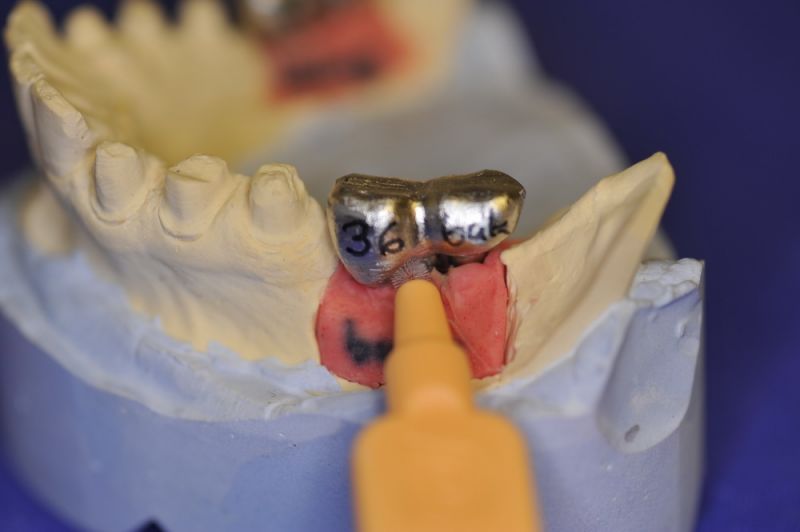

3. Sehr dünne Implantate, die von ursprünglich zwei je Kieferhälfte auf letztendlich drei je Kieferhälfte umgeplant werden mussten.

4. Notwendigkeit die Mundhygienefähigkeit der Arbeit auch unter sehr beengten Verhältnissen zu schaffen, um der Arbeit eine günstige Prognose mitzugeben.

2. Notwendigkeit der Intrerdentalraumhygiene. Zwischen den Zähnen einmal pro Tag. Zwischen den Implantataufbauten zweimal pro Tag.